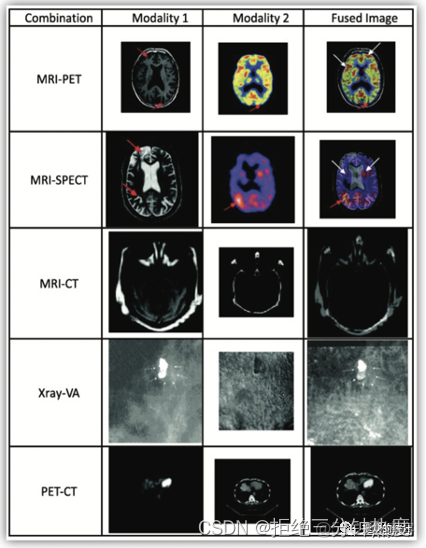

**“影像”:**常見的有平掃/增強CT、磁共振MRI、PET影像、超聲、X-ray等(甚至簡單至單張圖片也可以執行,但基本不做),圖像蒐集完畢後可能需要進行格式轉化、配準的內容。

模態比較。可以將多模態一一對比、或者融合做比較,比如CT中的平掃、增強、能譜CT等,MRI中有T1WI、T2WI、FLAIR、SWI、PWI、SWAN、灌注DSC等不同序列圖像;PET影像中根據藥物不同也可以得出不同種類影像,如FDG、MET、PSMA等藥物;對比劑增強;PET/CT融合圖像;PET/MR融合圖像等。